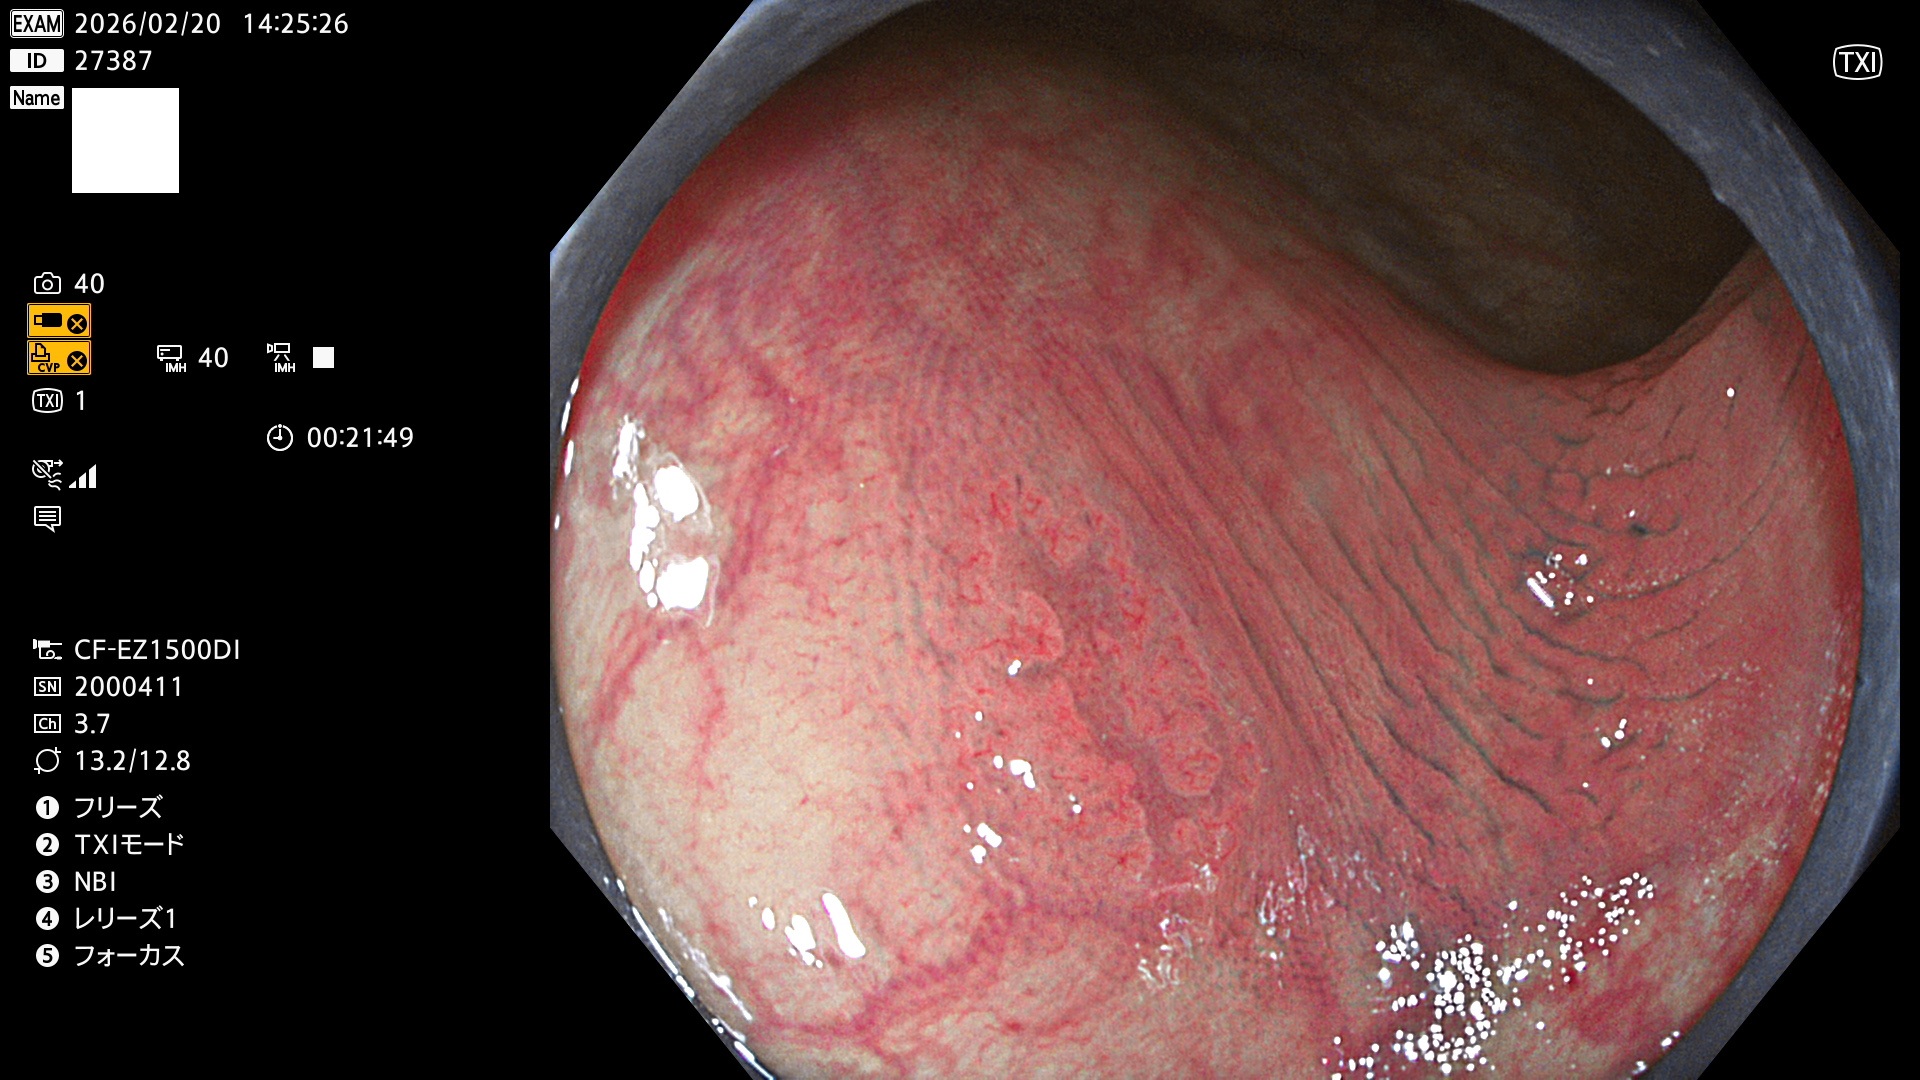

完全に平坦な物をUb、陥凹している物をUcと呼びます。Ubは認識が困難で、Ucはびらん(炎症)と紛らわしいために見落とされやすく、「内視鏡後・大腸癌」の原因になります。

2026年2月19日〜2月23日の4日間(40件)で3個 (Uc_ADR=3個/40人=8%)